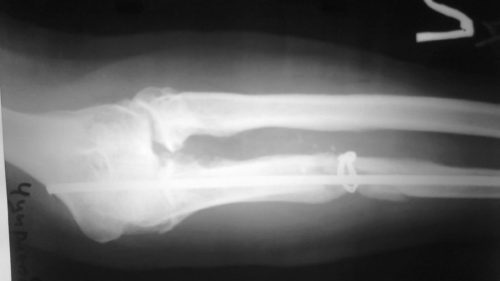

Решающее значение для диагностики ложного сустава имеет рентгенологическое исследование.

Для того чтобы определить наличие патологии, в обязательном порядке делают несколько снимков в разных проекциях: две перпендикулярные и дополнительные косые. На снимках можно увидеть наличие суставной щели между костями, которая имеет неровные очертания. Наиболее широкая щель встречается при гипертрофированном типе образования.

Края костных отломков сглажены, закруглены. Иногда на рентгенографическом снимке можно увидеть, как один из отломков в общих чертах напоминает суставную впадину, а другой похож на головку кости, входящей в эту впадину. Помимо этого костно-мозговая полость, расположенная между ними, зарастает с формированием замыкательной пластинки. Для того чтобы оценить степень и интенсивность происходящих патологических процессов, назначают дополнительное радионуклидное обследование.